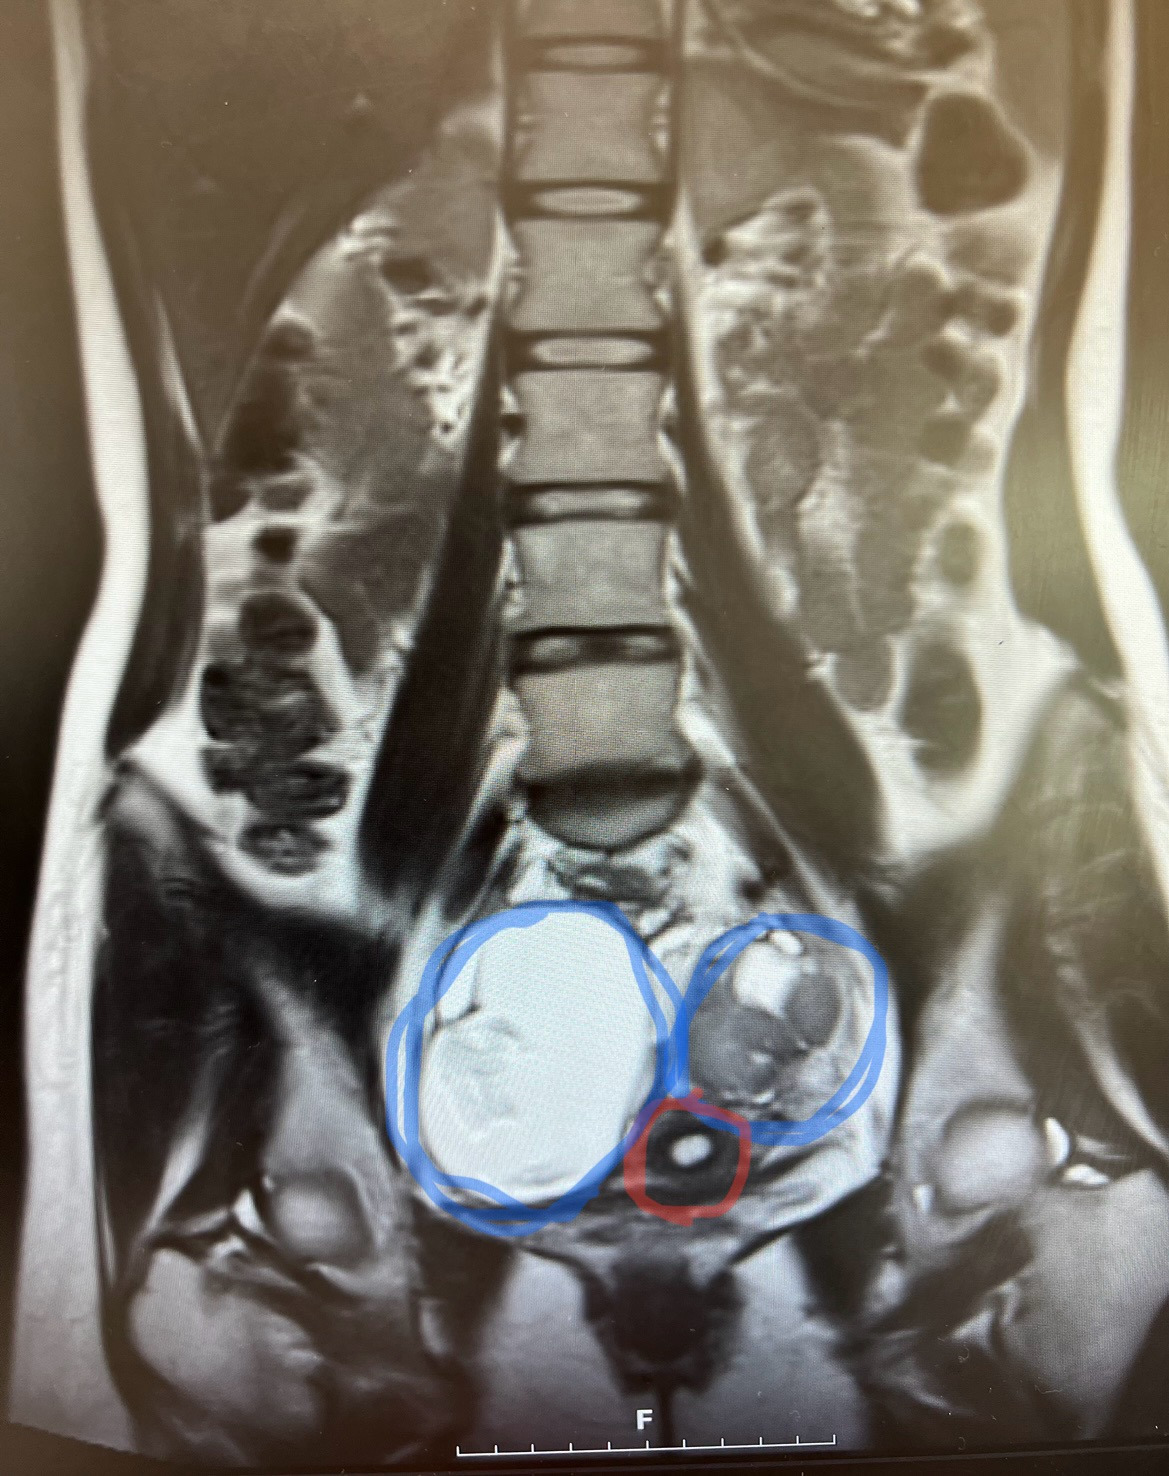

이것은 나의 MRI 사진이다. 저기 보이는 빨간 동그라미가 자궁이고, 양쪽에 있는 파란 동그라미가 그동안 나를 힘들게 해 왔던 통증의 원인이며, 고통의 바탕이자 오늘날의 내가 제거해야 할 혹이라 불리는 그것이다.

솔직히 조금 놀랐다. 초음파 사진으로 봤을 땐 그다지 와닿지 않던 혹의 크기가 MRI상으로 너무나 적나라하게 드러났기 때문이다. 자궁과의 차이를 보라! 4배나 크지 않은가.

의사 선생님 曰 배가 혹으로 꽉 찬 상태입니다.

이 말이 정답이었다. 나잇살이라 여겼던 아랫배의 실체는 지방이 아닌 종양이었고, 배 한가득 자리를 잡을 때까지도 나는 이 사실을 모르고 있었다. 무심한 건지, 둔감한 건지.